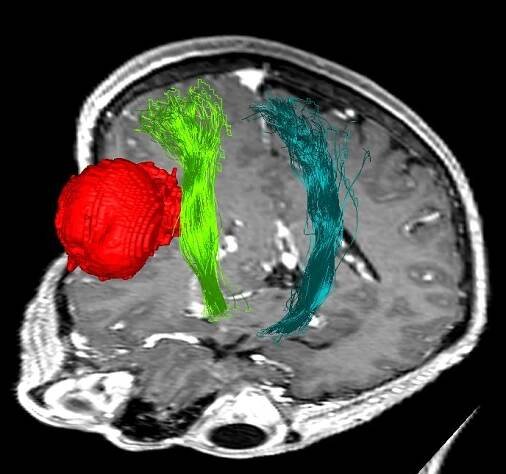

tumor-pyramidove-drahy